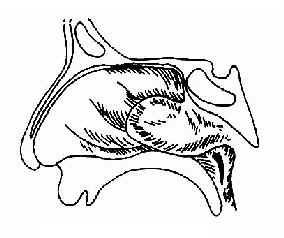

(三)鼻咽镜检查:可见鼻咽部有圆形、淡红色肿物,表面光滑,血管清晰可见。触诊肿物质硬、固定、易出血,前鼻镜检查有时鼻腔可见淡红色肿物(图12-7)。

图12-7 鼻咽血管纤维瘤